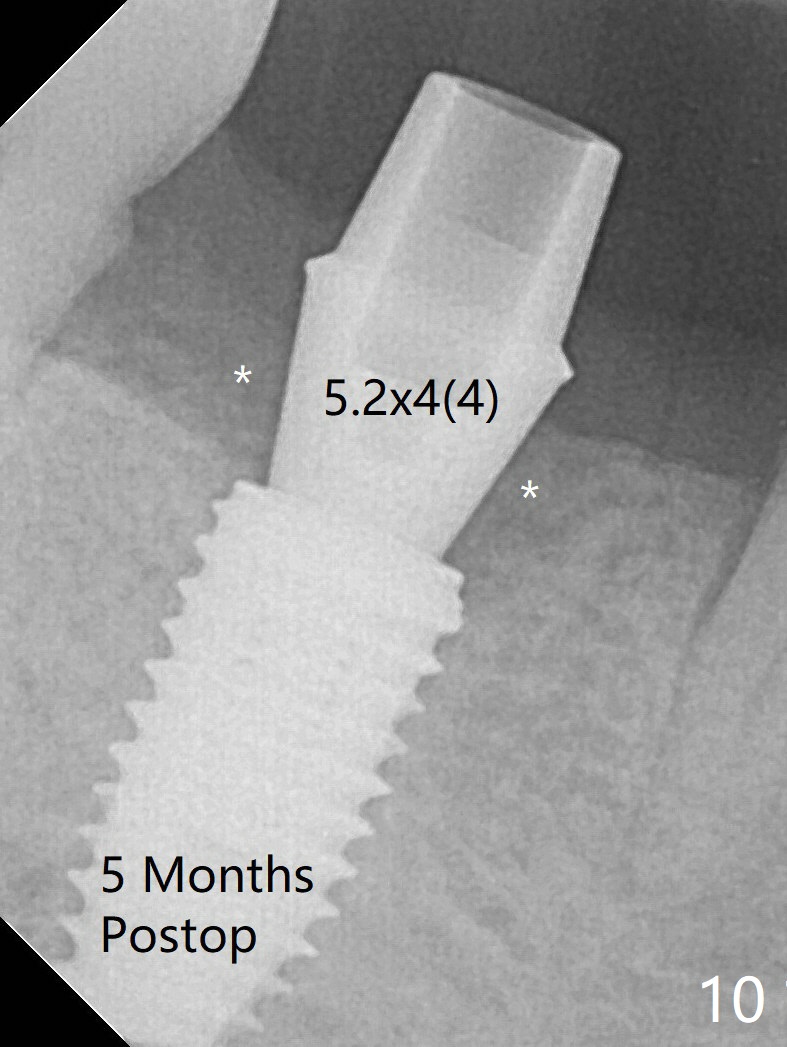

With 9 mm offset, the cylinder portion of the 2.2x8.5 mm drill does not engage to the metal sleeve of the guide at #28 after pointed drill (Fig.1). This issue could be solved with 12 mm offset, although it has no ill effect in this case. Fig.2 shows the site of #28 immediately before bone expansion and after use of 2.2x11.5 mm drill and small-scaled ridge split (^). The bone is so hard that the bone expansion is minimal (Fig.5) with autogenous bone graft and implant placement (Fig.4). There is the bone buccal to the implant clinically. A 5x10 mm implant is placed at #31 in the same appointment (Fig.3). Because of inability to masticate on the left (#18 root fracture with infection), the patient wants to restore #28 and 31 implants 3 months postop (Fig.6,7). The implant at #28 is removed while the healing abutment is being un-torqued without noting bone loss mesially (Fig.7 * (next similar case)). Bone graft is placed (Fig.8 (*),9). Pay attention radiolucency next the apex of the neighboring tooth (Fig.9 ?) before re-placement of an implant. The patient is upset, since he cannot eat. Two weeks later, a 6.5x4(4) mm cemented abutment is placed with 25 Ncm at #31 with a provisional for progressive loading for 2 weeks. Impression is taken. Two weeks later, a permanent crown is cemented without removing the underlying abutment. Two days later, the crown/abutment dislodges; a 6.8x6 mm healing abutment is placed. Eight days, it is difficult to reseat the existing crown and abutment. The mesiodistal edentulous space is limited as well. A 5.2x4(4) mm cemented abutment is able to be seated and torqued (30 Ncm) smoothly; in fact the clearance from the crestal bone (Fig.10 *) is not ample. If the abutment screw becomes loose in function, a profile drill should be used or a 4.5 mm in diameter abutment be placed. The abutment seems to remain in place immediate post cementation (Fig.11). Implant failure is probably due to no socket preservation (buccal plate atrophy) and too early restoration.